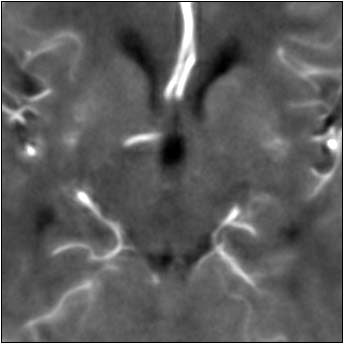

Finally they tested an anisotropic filter, which treats different image vectors differently. Anisotropic filters use the magnitude of local intensity gradients to determine which object edges should be preserved compared to less significant gradients.

In contrast, the anisotropic filter preserved 96% of the arterial signal, while overestimating blood volume by just 4%. Visually, the tissue and vasculature were both clearly delineated.

| Top image: original CT perfusion data shows brain parenchyma and opacified blood vessels (white), as well as substantial image noise. Middle image: same CT data after Gaussian filtering, which reduces image noise, but also reduces signal intensity in the blood vessels and distorts the signal in areas surrounding the vessels. Bottom image: Same data following application of anisotropic filter, which reduces image noise while preserving tissue boundaries. The boundaries are preserved by elongating the filter in a parallel orientation with the edges, such that the filter remains sufficiently large for appropriate noise reduction, but avoids mixing of several tissue types. All images courtesy of Marcel Quist. |

"There's one winner here, and the anisotropic filter performs best overall," he said. "Overall signal preservation is essential for quantitative analysis, and that's why we have included this anisotropic filter in our software."